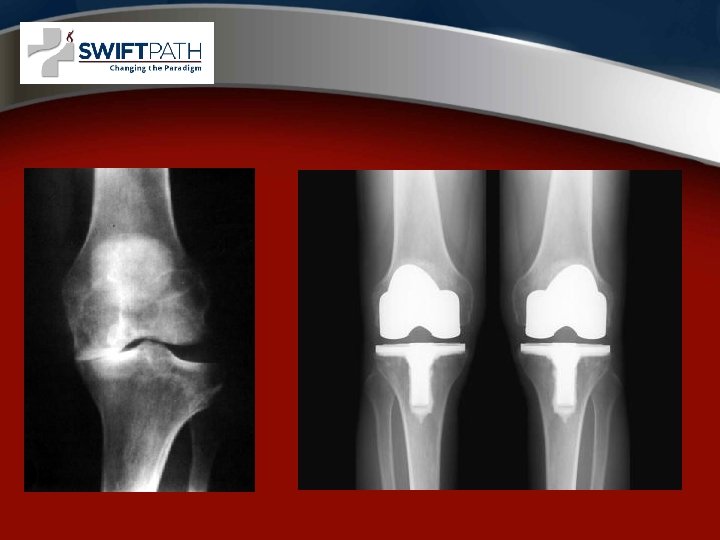

Surgical options • Arthroscopy • Partial Knee Replacement • Total Knee Replacement

MIS Knee Replacement • • Faster Recovery Improved Quads Function Less Pain Smaller Incisions Better ROM More Radiographic Outliers Computer Navigation Recommended